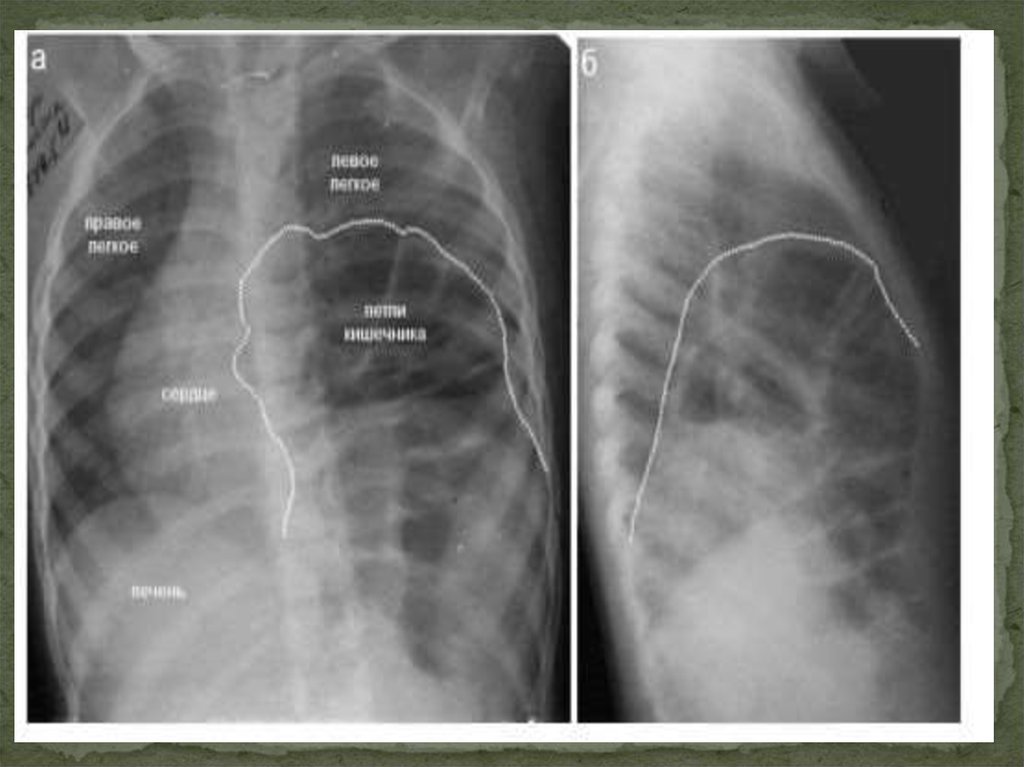

Диафрагмальные

ретрокостостернальные (справа — треугольника

Морганьи, слева — Ларрея)

пояснично-рёберные (Бохдалека)

сухожильного центра диафрагмы

(преимущественно — паракавальные грыжи)

грыжи пищеводного отверстия диафрагмы (ГПОД):

скользящие (аксиальные) и параэзофагеальные